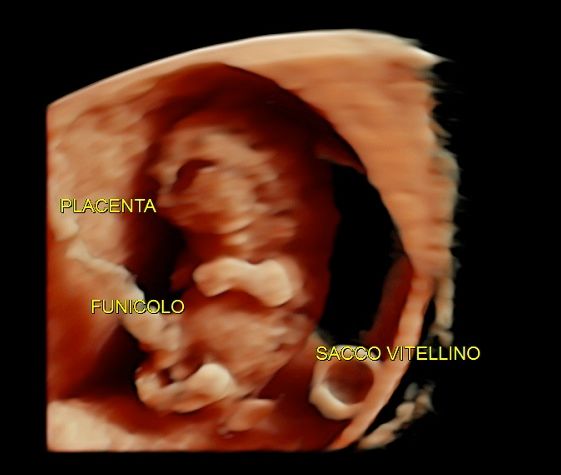

Foto e video